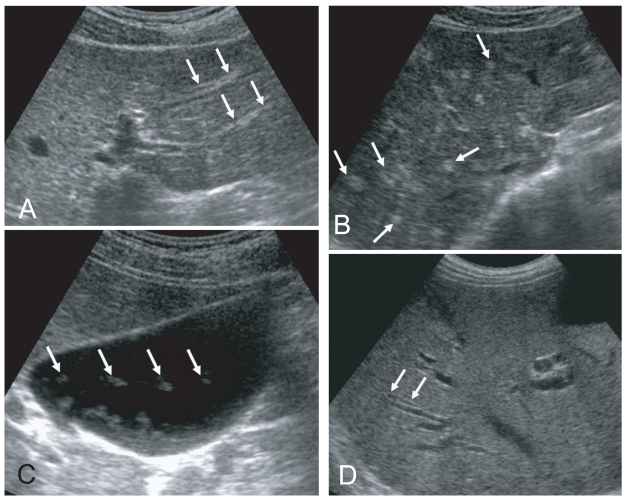

Fig. 2

Liver sonograms of clonorchiasis. A. In a 57-year-old man, transverse scan of the left hepatic lobe, showing mild dilatation of the intrahepatic bile ducts (arrows). B. In a 56-year-old man with the increased periductal echogenicity (arrows) along the dilated intrahepatic bile ducts. C. Oblique scan of the gallbladder of a heavily - infected Chinese man with several floating echogenic foci (arrows), which probably indicate worms or desquamated materials. D. Mild dilatation of the intrahepatic bile ducts in the central liver of a cured 60-year-old man.

Fig. 2 Liver sonograms of clonorchiasis. A. In a 57-year-old man, transverse scan of the left hepatic lobe, showing mild dilatation of the intrahepatic bile ducts (arrows). B. In a 56-year-old man with the increased periductal echogenicity (arrows) along the dilated intrahepatic bile ducts. C. Oblique scan of the gallbladder of a heavily - infected Chinese man with several floating echogenic foci (arrows), which probably indicate worms or desquamated materials. D. Mild dilatation of the intrahepatic bile ducts in the central liver of a cured 60-year-old man.

Sonographic findings of diffuse dilatation of the intrahepatic bile ducts and increased periductal echogenicity are known to well reflect pathological changes associated with clonorchiasis (Fig. 2) (Lim et al., 1989; Hong et al., 1994). Sonography is considered a good tool for the diagnosis of clonorchiasis, particularly in cases with a moderate or heavy burden of worms. According to a prior study in Korea, sonography showed low sensitivity and low specificity in the diagnosis of active clonorchiasis (Hong et al., 1998). The study suggested that the low sensitivity was due to a light worm burden and that the low specificity was due to residual pathology after cure.

In a recent study conducted by us in China, increased periductal echogenicity and floating echogenic foci in the gallbladder were proposed as the 2 most significant sonographic findings of active clonorchiasis (Choi et al., 2004). Increased periductal echogenicity represents a thickening of the ductal wall according to mucosal hyperplasia and periductal fibrosis, and the floating echogenic foci indicate worms or desquamated material in the gallbladder (Figs. 2A, B, C) (Lim et al., 1989; Hong et al., 1994; Choi et al., 1999). In our study in China, increased periductal echogenicity showed a sensitivity and specificity for active clonorchiasis of 35% and 91%, respectively (Choi et al., 2004). Floating echogenic foci in the gallbladder had a sensitivity and specificity of 28% and 94%, respectively. However, floating echogenic foci within the gallbladder have been rarely documented in Korea (Lim et al., 1989; Lim, 1990).

In the past literature, diffuse dilatation of the intrahepatic bile ducts on sonographic examination has been considered a hallmark of clonorchiasis (Lim et al., 1989; Lim, 1990; Hong et al., 1994). Diffuse dilatation of the intrahepatic bile ducts was found in an about half (49-52%) of the control subjects in either present endemic area or past endemic area (Fig. 2D) (Hong et al., 1998; Choi et al., 2004). Thus, patients only with a dilatation of the intrahepatic bile ducts detected by sonography cannot be considered candidates for praziquantel treatment (Chen et al., 1994; Hong et al., 1998; Choi et al., 1999). In an experimental study, the histopathological specimens at 18 mo after treatment with praziquantel showed that periductal inflammation has almost resolved but moderate dilatation of the intrahepatic ducts and mucosal hyperplasia persisted (Choi et al., 1999). The periductal fibrosis minimally resolved.